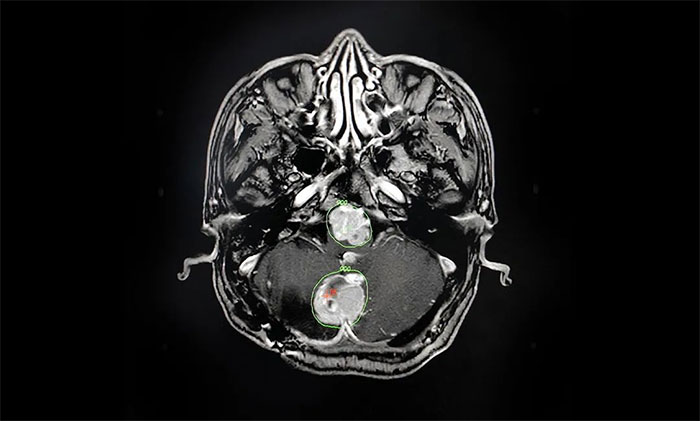

▲ MRI影像复查病灶明显缩小

在伽玛刀治疗后,汪先生身体状况良好,未出现明显并发症,经综合评估顺利出院。8月份,他遵照医嘱来院复查,MRI可见病灶较治疗前明显缩小。